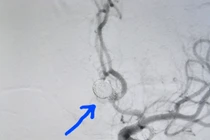

Nhiều nghiên cứu cho thấy tỉ lệ tồn tại phình mạch não có thể tới 5% dân số. Mỗi năm có khoảng 50000 người Mỹ bị đột quỵ do vỡ phình mạch não, 2/3 trong số đó chết hoặc để lại di chứng hết sức nặng nề.

Phình mạch máu não xảy ra rất đột ngột, khi phình mạch bị vỡ, người bệnh sẽ gặp nguy hiểm đến tính mạng. Phình mạch não có thể một hoặc nhiều lần, lần sau thường nặng hơn lần trước, tỷ lệ tử vong rất cao, thậm chí đột tử ngay.